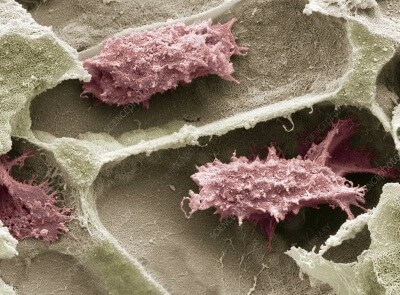

З-D Матрикс с сохраненными прочностными характеристиками и повышенной гидрофильностью.

100% коллаген (1 -3 типов) животного (крупно-рогатого скота) происхождения.